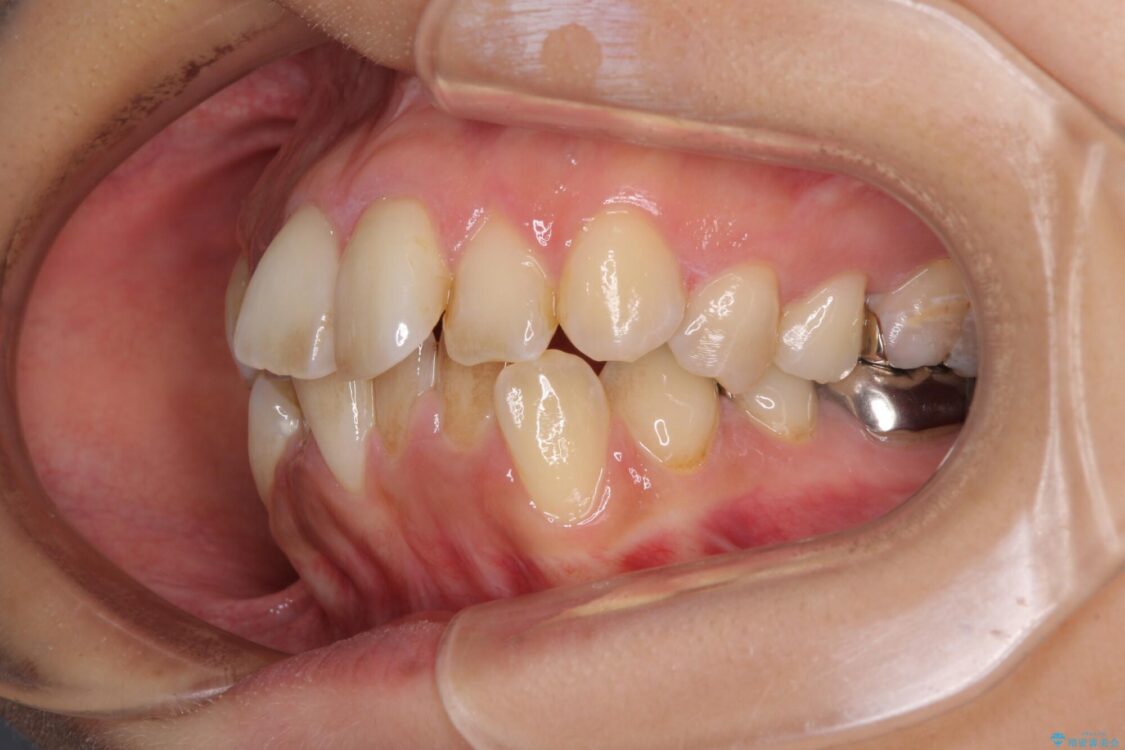

治療途中

• デコボコと口元の突出感 ハーフリンガルでの抜歯矯正 治療途中画像